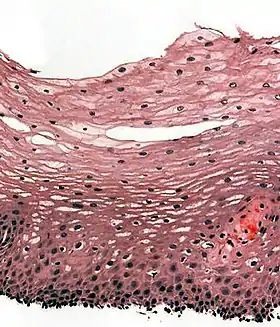

التشريح المجهري

للمريء عند البشر غشاء مخاطي يتألف من ظهارة مسطّحة مطبّقة متراصة لا تحوي كيراتين، وصفيحة مخصوصة ملساء، وعضلة مخاطية.[5] كما أن لظهارة المريء تقلّب سريع نسبيَّاً، وتخدم كطبقة وظيفية حامية ضد التأثيرات الساحجة (الكاشطة) للطعام. وفي العديد من الحيوانات تحتوي الظهارة على طبقة من الكيراتين.[18] هناك أيضاً نوعان للغدد، الغدد المريئية المفرزة للمخاط وهي موجود الطبقة تحت المخاطية، والغدد الفؤادية المريئية وهي مشابهة للغدد الفؤادية في المعدة وتقع هذه الغدد (أي الفؤادية المريئية) في الصفيحة المخصوصة وتكثر في نهاية العضو (المريء).[18][19] يمنح المخاط المُفرَز من هذه الغدد حمايةً للبطانة من الطعام.[20] تحتوي كذلك الطبقة تحت المخاطية على ضفيرة تحت مخاطية، وهي شبكة من الخلايا العصبية وهي جزء من الجهاز العصبي المِعَوِّيّ.[18]

أما الطبقة العضلية فتشتمل على نوعين من العضلات. الثلث العلويمن المريء يحتوي على عضلات مخططة، أما الثلث السفلي فيحتوي على عضلات ملساء، أما الثلث الأوسط فيحتوي مزيجاً من النوعين السابقين.[5] تترتب العضلات في طبقتين: تسير الألياف العضلية في إحداهما طوليَّاً، أما الأخرى تأخذ الألياف شكلاً حلقيَّاً في الأخرى، ويفصل بين هاتين الطبقتين الضفيرة العضلية المعوية وهي شبكة من الألياف العصبية المتشابكة، تساهم هذه الضفيرة في إفراز المخاط وفي تمعُّج العضلات الملساء في المريء. أما الطبقة الخارجيّة لجدار المريء فهي الطبقة البرَّانيّة (باللاتينية: adventitia) وهي موجودة في معظم طول المريء، وفي المنطقة البطنيّة تُغطَّى بغشاء مصليّ، وبهذا يتميّز المريء عن البنى الأخرى في السبيل الهضمي (أي بفقد للطبقة المصليّة في أجزائه غير البطنية).[5]